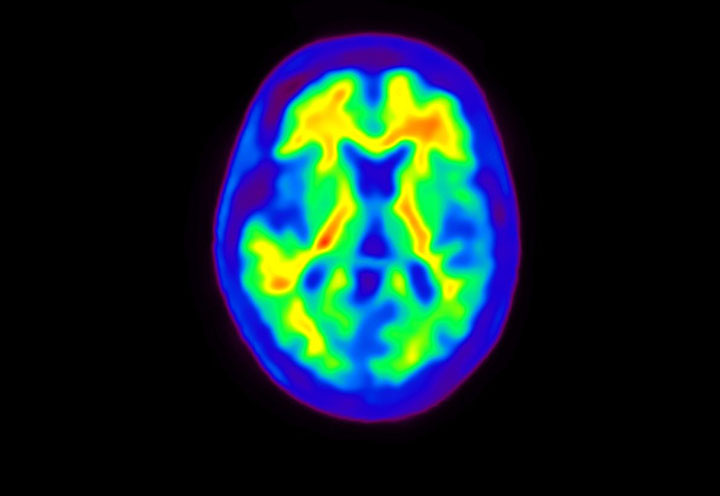

Head / Case4 : Amyloid

Courtesy : Kindai University Hospital

- Imaging protocol

- Injected dose: 3.21 MBq/kg, 18F-Flutemetamol

- Uptake time: 100 minutes

- Scan time: 20 minutes